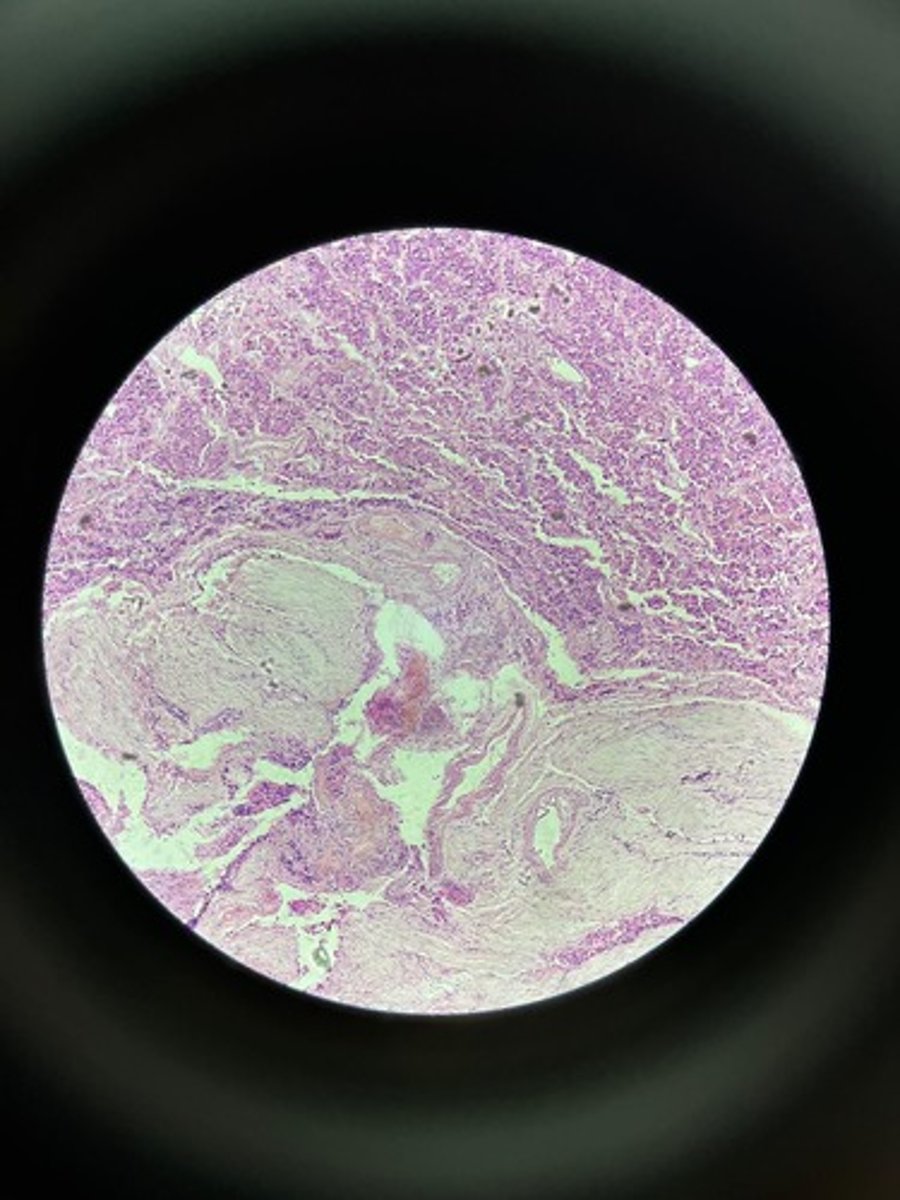

Lymph node HE

Lymph node HE

Lymph node HE

lymph node HE

Lymph node HE

Lymph nodes HE